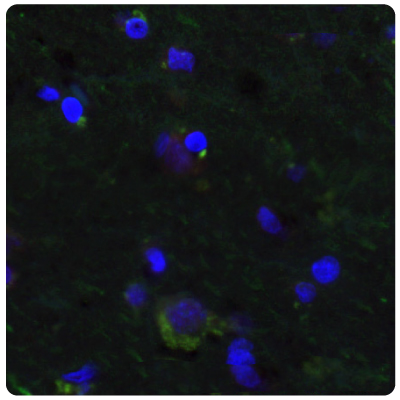

Immunohistochemistry (IHC) plays a vital role in distinguishing between different tumor types. Figures 1 and 2 show some examples of IDH1, ATRX, and GFAP multiplexed IHC-IF staining in different glioma grades.

Figure 1A.ATRX and GFAP in astrocytoma. Multiplexed IHC-IF staining of astrocytoma showing ATRX (nuclear, in red) and GFAP (cytoplasmic, in green) immunoreactivity in tumor cells using Anti-ATRX antibody and Anti-GFAP antibody. Nuclei were counterstained with DAPI (in blue).

Figure 1B.ATRX and IDH1 in oligodendrocytoma. Multiplexed IHC-IF staining of anaplastic oligodendroglioma showing ATRX (nuclear, in red) and IDH1 (cytoplasmic, in green) immunoreactivity in tumor cells using Anti-ATRX antibody and Anti-IDH1 antibody. Nuclei were counterstained with DAPI (in blue).